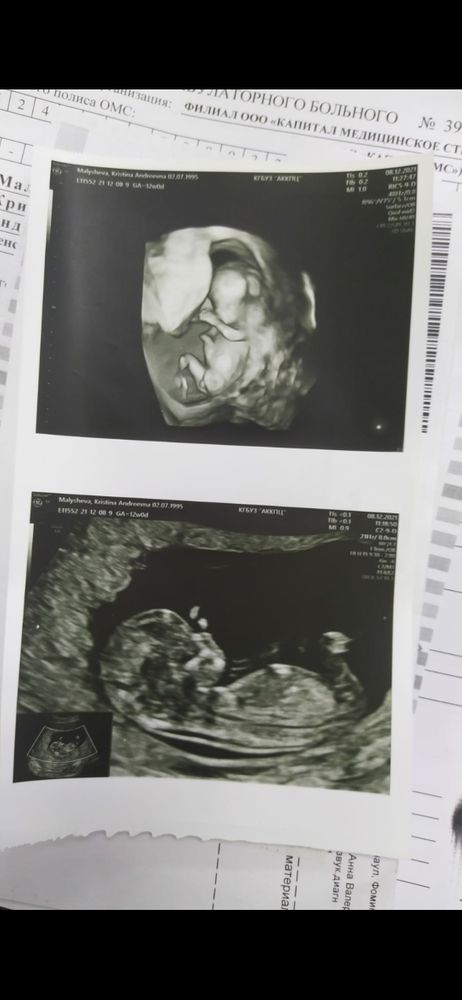

Не видно бугорка, на первой картинке там что-то между ножек, но великовато чтобы быть бугорком (думаю это пуповина, ну либо ножка в этом ракурсе так размыто выглядит) могу сказать чисто интуитивно, похоже что мальчик))))

Увидили между ног бугор, вот и утверждают 🤦. Мало кто вообще в теме, что это может быть пуповина, часть ноги и вообще на таком сроке оно там одинаково торчит. Помню тут у девушки между ног на узи болталось что-то размером с пол ноги ребёнка, так ответы поражали своей однообразностью 😆 хотя казалось бы, интернет у всех есть, ну прочитай что там как формируется))) На вашем фото не понятно, можно было бы по профилю посмотреть угол наклона, но мне кажется не попало в срез нужное место

На мой взгляд девочка) тк бугорок смотрит вниз, а не прямо) через месяц точно будете знать)

Вот если бы на втором фото был захвачен и половой бугорок ,то с такого ракурса можно было бы сказать )А так не понятно ,на первой фотке возможно и не оно )

Если то, что я на втором фото вижу - половой бугорок, то это скорее девочка, т.к. бугорок не вверх смотрит, а ближе к горизонтальному.

На верхнем фото что-то мальчуковское торчит, не? 🙈😄

Кристина Малышева, вот где ножки раздвинуты, там бугорок между ног, и он смотрит больше вниз, поэтому я за девулю